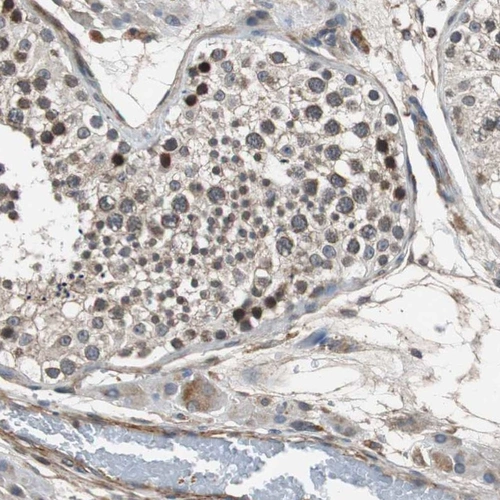

Immunohistochemistry analysis in human testis and salivary gland tissues using Anti-PITRM1 antibody. Corresponding PITRM1 RNA-seq data are presented for the same tissues.